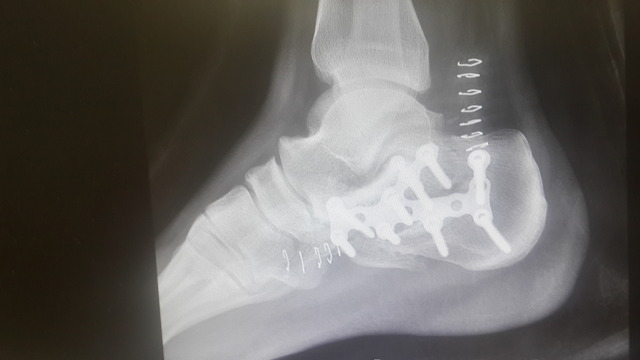

8월 20일 수술. 철심을 10개 박았네요. X-ray 사진은 아래와 같습니다.

수술 6주차에 찍은 X-ray 상엔...철심이 워낙 많아서 이거 뭐 뼈가 붙었는지는 잘 보이지도 않더라고요 ㅎㅎ.